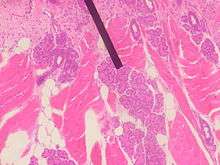

Von Ebner's glands, also called Ebner's glands or gustatory glands, are exocrine glands found in the mouth. More specifically, they are serous salivary glands which reside adjacent to the moats surrounding the circumvallate and foliate papillae just anterior to the posterior third of the tongue, anterior to the terminal sulcus.

Von Ebner's glands secrete lingual lipase,[1] beginning the process of lipid hydrolysis in the mouth. These glands empty their serous secretion into the base of the moats around the foliate and circumvallate papillae. This secretion presumably flushes material from the moat to enable the taste buds to respond rapidly to changing stimuli.